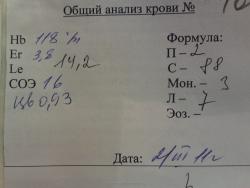

А вот в ОАК динамика есть (на фоне дезинтоксикации видимо)

От 2.03.11

И от 03.03.11